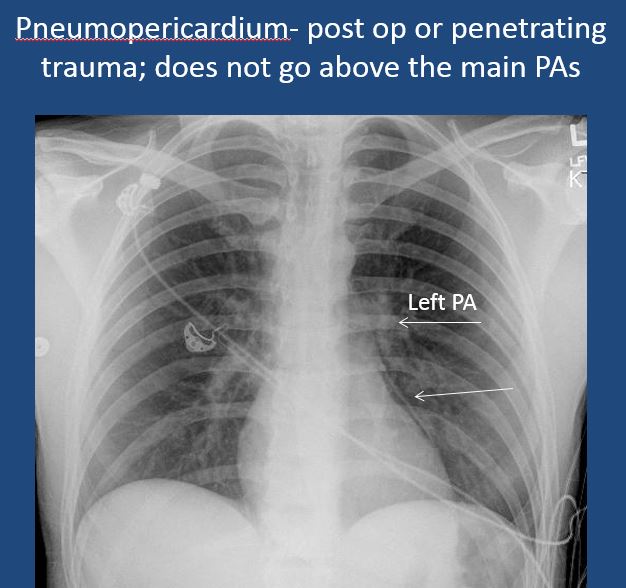

There is pneumopericardium. |

No | NA |